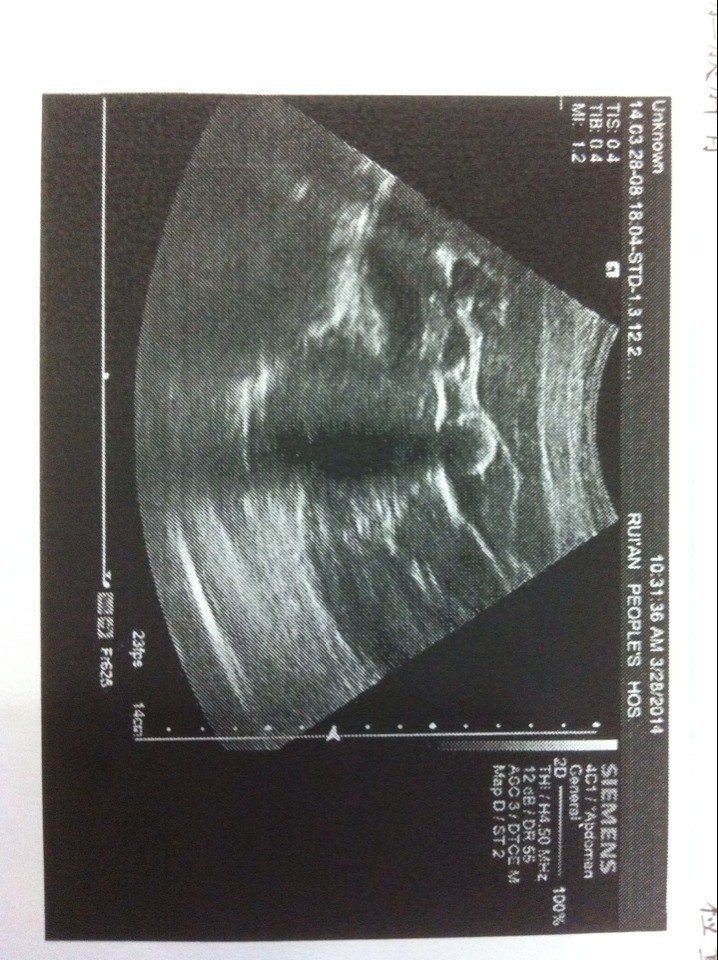

被查有胆结石 没什么感觉怎么处理好!28岁还想生小孩子 是做了再要孩子还是不用做可以要孩子 。 点击展开 匿名用户 2014-03-29 17:22 为您推荐: 其他回答 这种结石的危害在于大多数情况下没有问题,但是万一嵌顿了需要急诊手术,那么孕期一旦嵌顿了就会非常麻烦,你是保胎还是手术?到时候会两难,还会受更多罪,所以。。。 那寄翠_t3mA 2014-03-29 17:27 相关问题 一岁零4个月的小孩子得了流沙性胆结石该怎么办? 婴儿和小孩子吃含三聚氰胺的奶粉会造成胆结石吗?